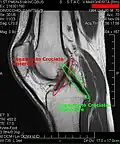

Os ligamentos são os estabilizadores primários para a translação anterior e posterior, angulação vara e valga, e para a rotação interna e externa da articulação do joelho. O ligamento cruzado anterior (LCA) é a restrição predominante ao deslocamento tibial anterior, pois aceita 75% da força em extensão completa e um adicional de 10% (até 90.º) de flexão do joelho. Com esses dados fica evidente que o LCA é o mais exigido no dia a dia de uma pessoa saudável, que pratica esporte por lazer ou profissão.

ligamento cruzado anterior (LCA)dentrocôndilo lateral do fêmurárea intercondilar anteriorO papel do LCA é prevenir o deslizamento anterior excessivo da tíbia em relação ao fêmur

ligamento cruzado posterior (LCP)dentrocôndilo medial do fêmurárea intercondilar posteriorA lesão deste ligamento é incomum, mas pode ocorrer resultando de uma força de tração traumática do ligamento. Este ligamento previne o deslizamento posterior excessivo da tíbia em relação ao fêmur.